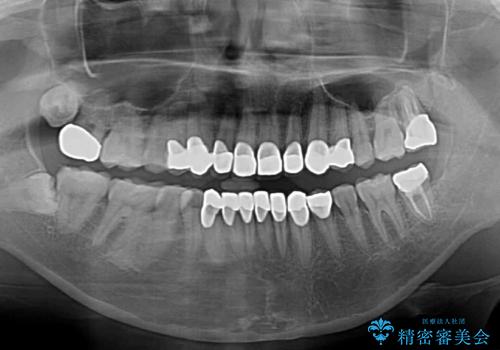

歯肉移植術による根面被覆を行うかどうかは非常に悩まれていましたが、歯肉が覆われたことで長く見えていた歯の長さが整い、きれいな前歯の仕上がりとなりました。